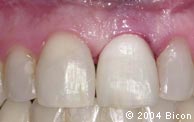

56. | 戴入基台冠5天后的唇侧观显示健康的牙龈,及其变黑处被很好的掩饰。。 |